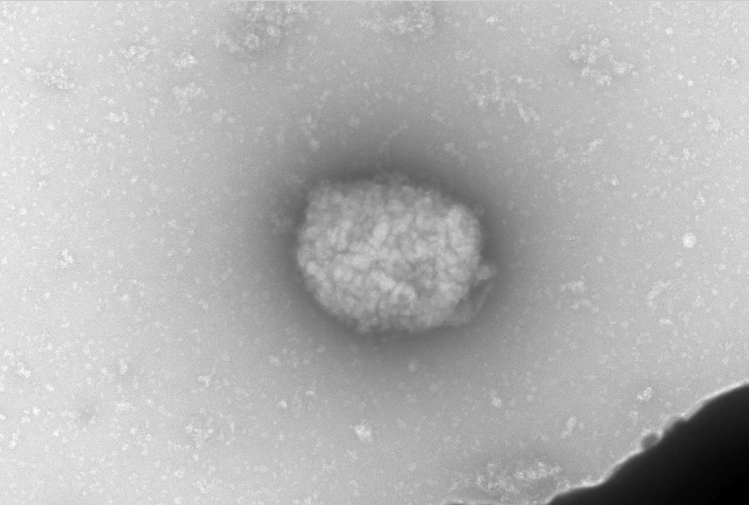

Los extranjeros que lleguen a China y muestren síntomas de viruela del mono deberán someterse a pruebas de etiología

Todos los viajeros que entren en China desde el extranjero deberán someterse a pruebas de viruela del mono aparte de las de COVI-19, informó el rotativo oficial Diario del Pueblo, que cita una nueva guía de prevención de la enfermedad publicada por la Comisión Nacional de Sanidad.